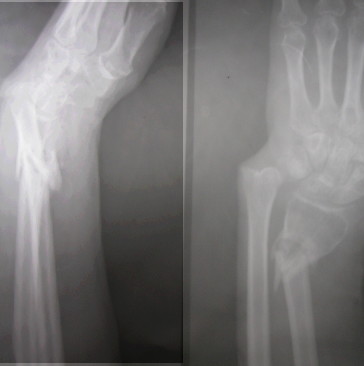

Dear All,Presenting this on behalf of a colleague of mine.52 years old healthy male sustained a closed fracture of his distal forearm 3 mths ago.

Due to so many other injuries sustained by him, this has been inadequately treated and he has ended up today like this. Very prominent distal ulna and a mobile fracture distal radius. No infection. Wrist flexion, extension fully free and so also the fingers. He has a good grip too. He wants correction of this deformity.I have opined as follows. Exfix with two pins in the distal radius and two proximally. Distract gradually till the DRUJ is properly aligned. 1)If one is lucky some bone would have formed in between which may be good enough. Continue ExFix till it is solid. 2) If we find that no bone is forming by 2 weeks, we can distract a bit faster Once the DRUJ is aligned and there is gap left, we can put in a small piece of fibula under tension and continue the ExFix till it is consolidated. If one is used to, a plate can be used to fix the radius along with the graft. This will shorten the ExFix time Suggestions are welcomeV M Iyer. Iyer Orthopaedic Centre, 103,Railway lines Solapur India

Is it possible to see an xray of the entire forearm including the elbow?

The image has been cropped and so it is not possible. The forearm and the elbow do not show anything abnormal,

I think that your suggestion is reasonable. I doubt an acute correction will gain anatomic length of the radius. I would be inclined to plate and bone graft once length is attained.

May not be able to get full length of radius but a good plan. End game may be to shorten ulna , plate and bone graft radius. Keep us posted from time to